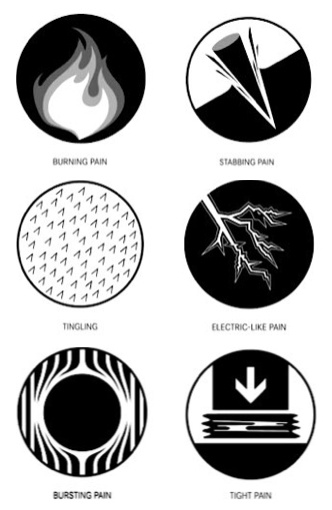

" Pain is a messenger you should never ignore "Never ignore pain - it is the early warning that you need to listen to. Whether a leaking filling or crown or the first beginning of decay or an infection. Acting early will save you time, money and discomfort.Thomas has a variety of techniques to get you out of pain quickly and his many anaesthetic techniques which includes intraosseous, always follow the strongest numbing sprays means he always succeeds in making treatment completely comfortable. Follow-up visits are normally organised before you leave and full instructions are always given for any treatment done.Always try to come with information about any medications you have taken and what brings on the pain.

There are a number of ways to decide whether you need root canal treatment and the specific x-rays, scans and tests help diagnose your problem.An important sign is the type of pain you have been having with a tooth. It helps me decide if a tooth is in need of treatment and even if it saveable.

The pain you have experienced and are currently in - happens to be very important messenger.

That is why I suggest that as much as possible, that you try to avoid painkillers in the hours before your initial root canal consultation. This is especially important when it is unclear to your regular dentist about which tooth is causing the problem.